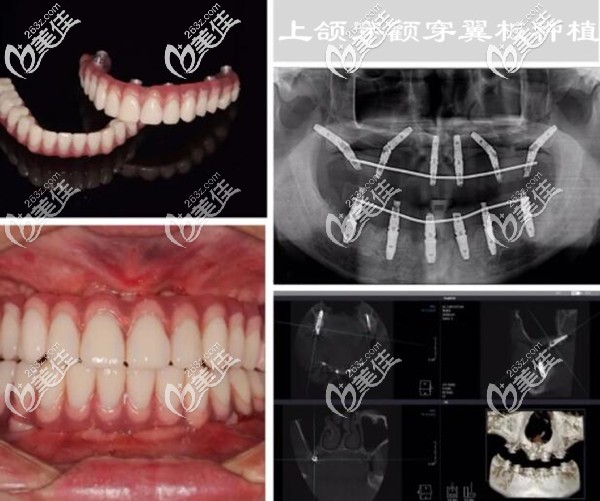

我今年50歲,是做穿顴穿翼板種植牙的受益者;從戴單顆的烤瓷牙到全口的活動假牙,已有10多年了;現(xiàn)在的牙槽骨萎縮、條件極差,假牙動不動就掉了,常年吃不好飯,腸胃也跟著受累。

因為,牙槽骨量太少,做傳統(tǒng)的種植牙要大量植骨,而且還要等3個月左右才能種牙。后來,上頜做的是雙側穿翼板種植,不用植骨;整個手術過程用了2個小時左右(不過手術前挺麻煩的,做了好多檢查)。

其實,我在做手術前也很緊張、很擔心,怕手術會有風險,擔心留下啥后遺癥;不過看了術后多次復查的CT片,我終于放心了。

下面是我做穿顴穿翼板種植牙后的照片和CT片▼